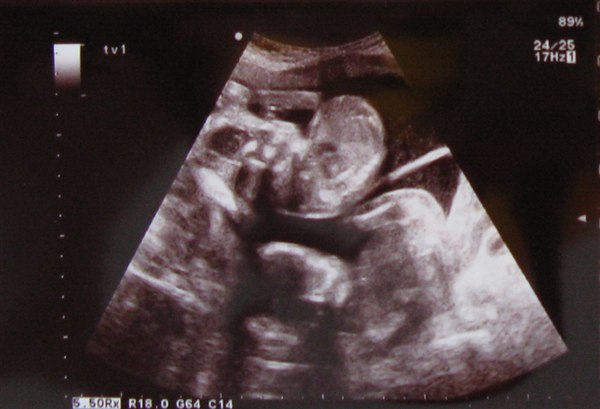

Det blev bekræftet at det ER en dreng og en pige

De er begge i topform og uden nogle "produktionsfejl". De er store og fine. Alvin har en lidt tykkere mave end Viola (hun har nok bare arvet sin mors hvepsetalje...host host).

Alt i alt en super god oplevelse. Der blev taget et "køjesengsbillede". Det er ikke så tydeligt, men det eneste som har været muligt at tage. Ved alle andre scanninger har det ikke været muligt at fange dem begge to på samme billede.